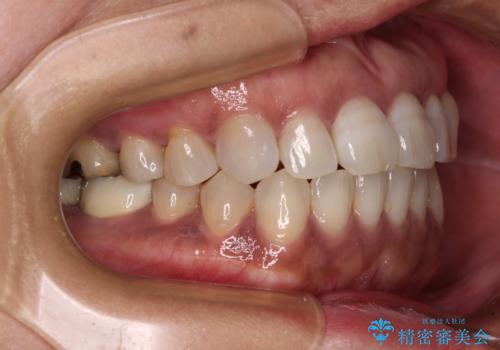

極端な上下前歯の開咬を改善 オープンバイトのインビザライン矯正

- 上下前歯の隙間を気にして来院された患者様です。

開咬の治療は、前歯を閉じるように動かすとともに、上下臼歯を圧下(骨内にめり込ませる)させることで進めて行きます。

インビザラインは臼歯の圧下を効果的に行えるため、インビザラインを用いて矯正治療を行うこととしました。

治療前に、いくらインビザライン矯正がオープンバイトを得意としているとは言え、さすがに限界があるだろうと思っておりましたが、前歯でレタスが噛めるまで改善することができました。